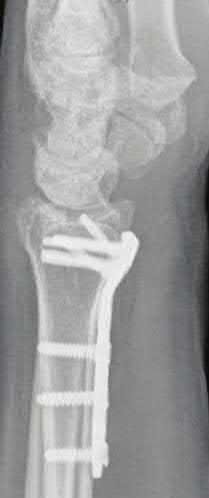

Question 15

A 62-year-old female presents with a pathologic subtrochanteric femur fracture. Her laboratory workup reveals hypercalcemia, anemia, and an elevated total serum protein.

Serum protein electrophoresis demonstrates a monoclonal spike. Which of the following best describes the underlying pathophysiology responsible for the lytic bone lesions in this condition?

Explanation

Multiple myeloma, a malignancy of plasma cells, causes characteristic osteolytic bone lesions through an uncoupling of bone remodeling. Myeloma cells upregulate osteoclastogenesis by secreting factors such as Macrophage Inflammatory Protein-1 alpha (MIP-1α) and Receptor Activator of Nuclear factor Kappa-B Ligand (RANKL). Concurrently, they inhibit osteoblast activity (via factors like DKK1 and sclerostin). PTHrP is classically associated with solid metastatic tumors (e.g., breast, lung), not myeloma.